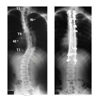

脊柱側湾症について

より侵襲の少ない手術方法と術後の日常生活について